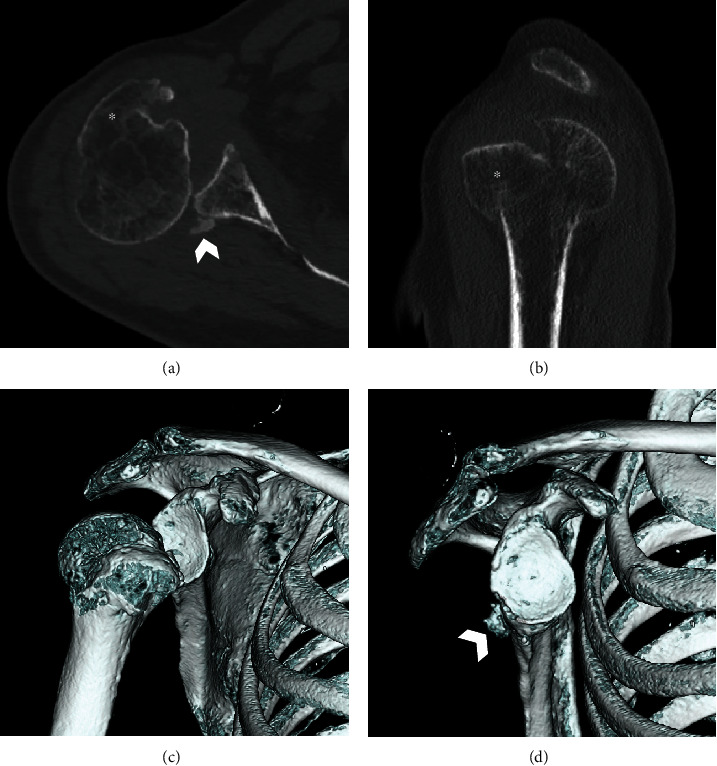

Posterior dislocation of the shoulder joint is a rare condition. It is often misdiagnosed owing to a lack of evident clinical features compared with anterior shoulder dislocation, and inappropriate radiological examination. We present a case of chronic posterior fracture dislocation treated with greater tuberosity osteotomy. A 66-year-old man was injured in a fall while carrying a drone. He was referred to our hospital following 3 months of conservative treatment at a nearby clinic, without reduction of the posterior dislocation. Physical examination revealed a prominent reduction in shoulder joint range of motion and shoulder pain. Radiological examination revealed posterior shoulder dislocation associated with greater tuberosity malunion and a small bone fracture of the posterior portion of the glenoid. Open reduction and internal fixation, including greater tuberosity osteotomy, were performed. Although subluxation of the posterior dislocation persisted postoperatively, the humeral head gradually returned to its centric shoulder joint position owing to rotator cuff force coupling. At 24-month follow-up, the patient showed excellent shoulder results.